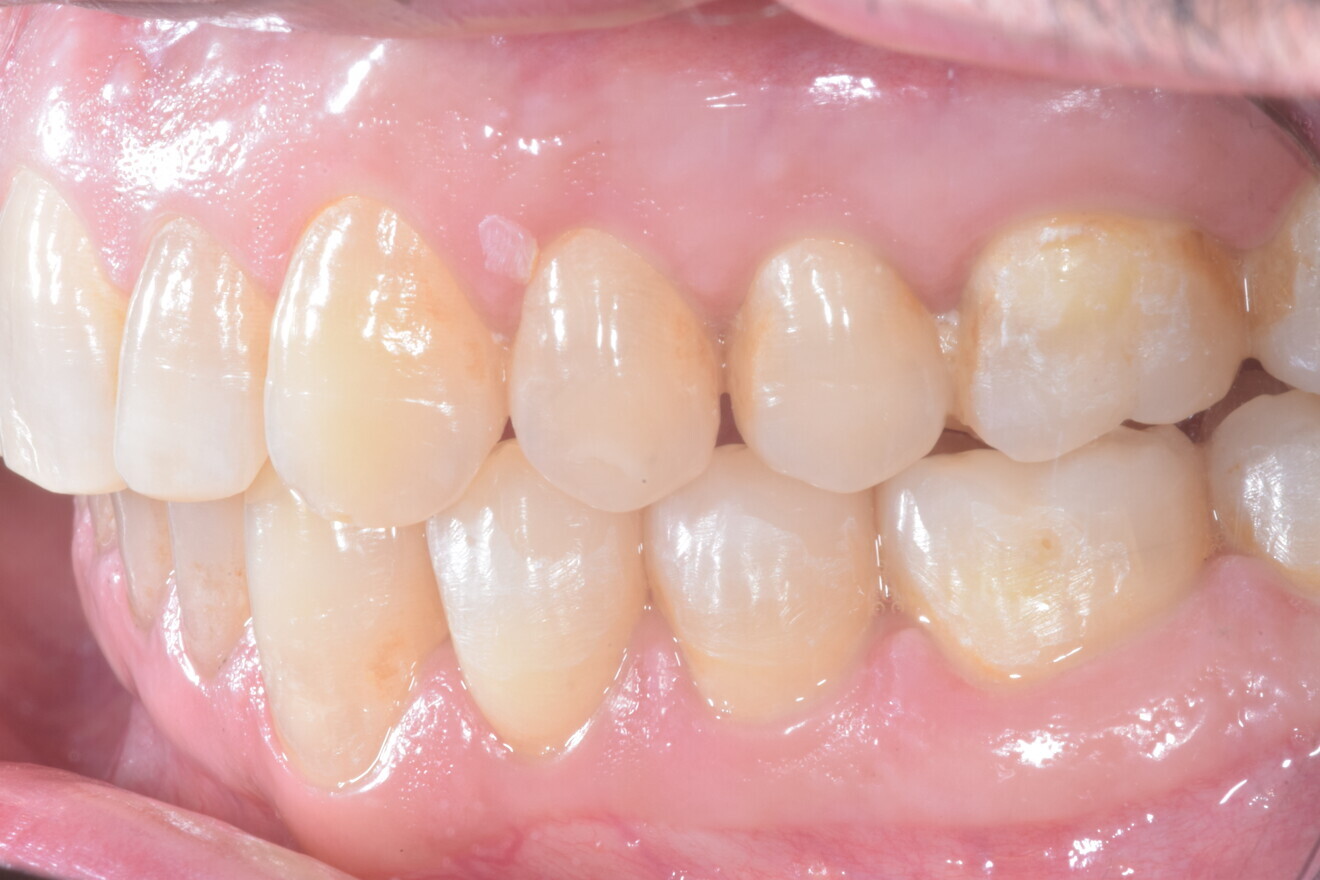

Fig. 13

Fig. 14

Fig. 15

Fig. 16

Fig. 17

Fig. 18

A 37-year-old male patient presented with the chief need for re establishing anterior alignment in both arches. Facial analysis showed a short face with a flat profile but proper chin projection (Figs. 9–12), and clinical examination revealed a skeletal Class I (ANB = 0.89°) and dental Class I malocclusion with severe deep bite (almost 100%), a deep curve of Spee, normal maxillary central incisor torque (Ui–FH = 110°), mild maxillary crowding and moderate mandibular crowding (Figs. 13–18). The deep bite components were represented in this patient by the severe skeletal condition of hypo divergent pattern (FMA = 14.24°) with normal maxillary and mandibular incisor inclination and decreased gonial angle (110.46°). Analysis of the cephalometric radiograph indicated a reduced lower anterior facial height, combined with a hypo-divergent pattern (Fig. 19). The only treatment option suggested was orthodontic treatment with aligners for deep bite correction with all the features described (bite ramps, pressure area, 3D curve of Spee levelling, Class II elastics and heavy occlusal contacts).